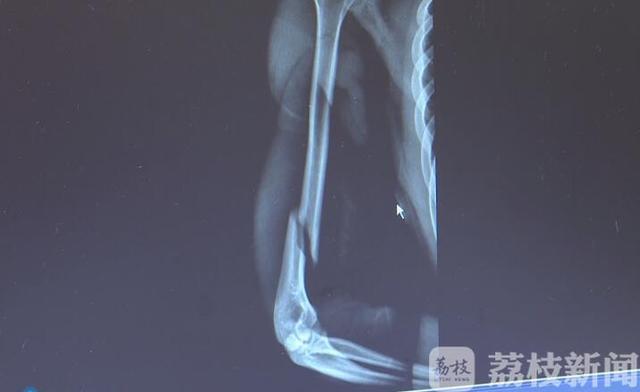

荔枝新闻讯很多人在较量力气的时候 , 喜欢用“扳手腕”来分高低 。 近日 , 湖南长沙20岁的小肖在寝室与同学比试扳手腕 , 僵持了40秒左右后 , 他猛然发力想要扳倒对手 , 却听见自己的手臂咔嚓一声 , 断了 。

医生诊断这是一个长的螺旋形骨折 。 意外发生后 , 跟小肖一起扳手腕的小刘一直在医院照顾他 。 小刘是同学们公认的“大力士” , 扳手腕那天 , 小刘和小肖一直僵持不下 , 最后小肖突然发力却把自己手给扳断了 。